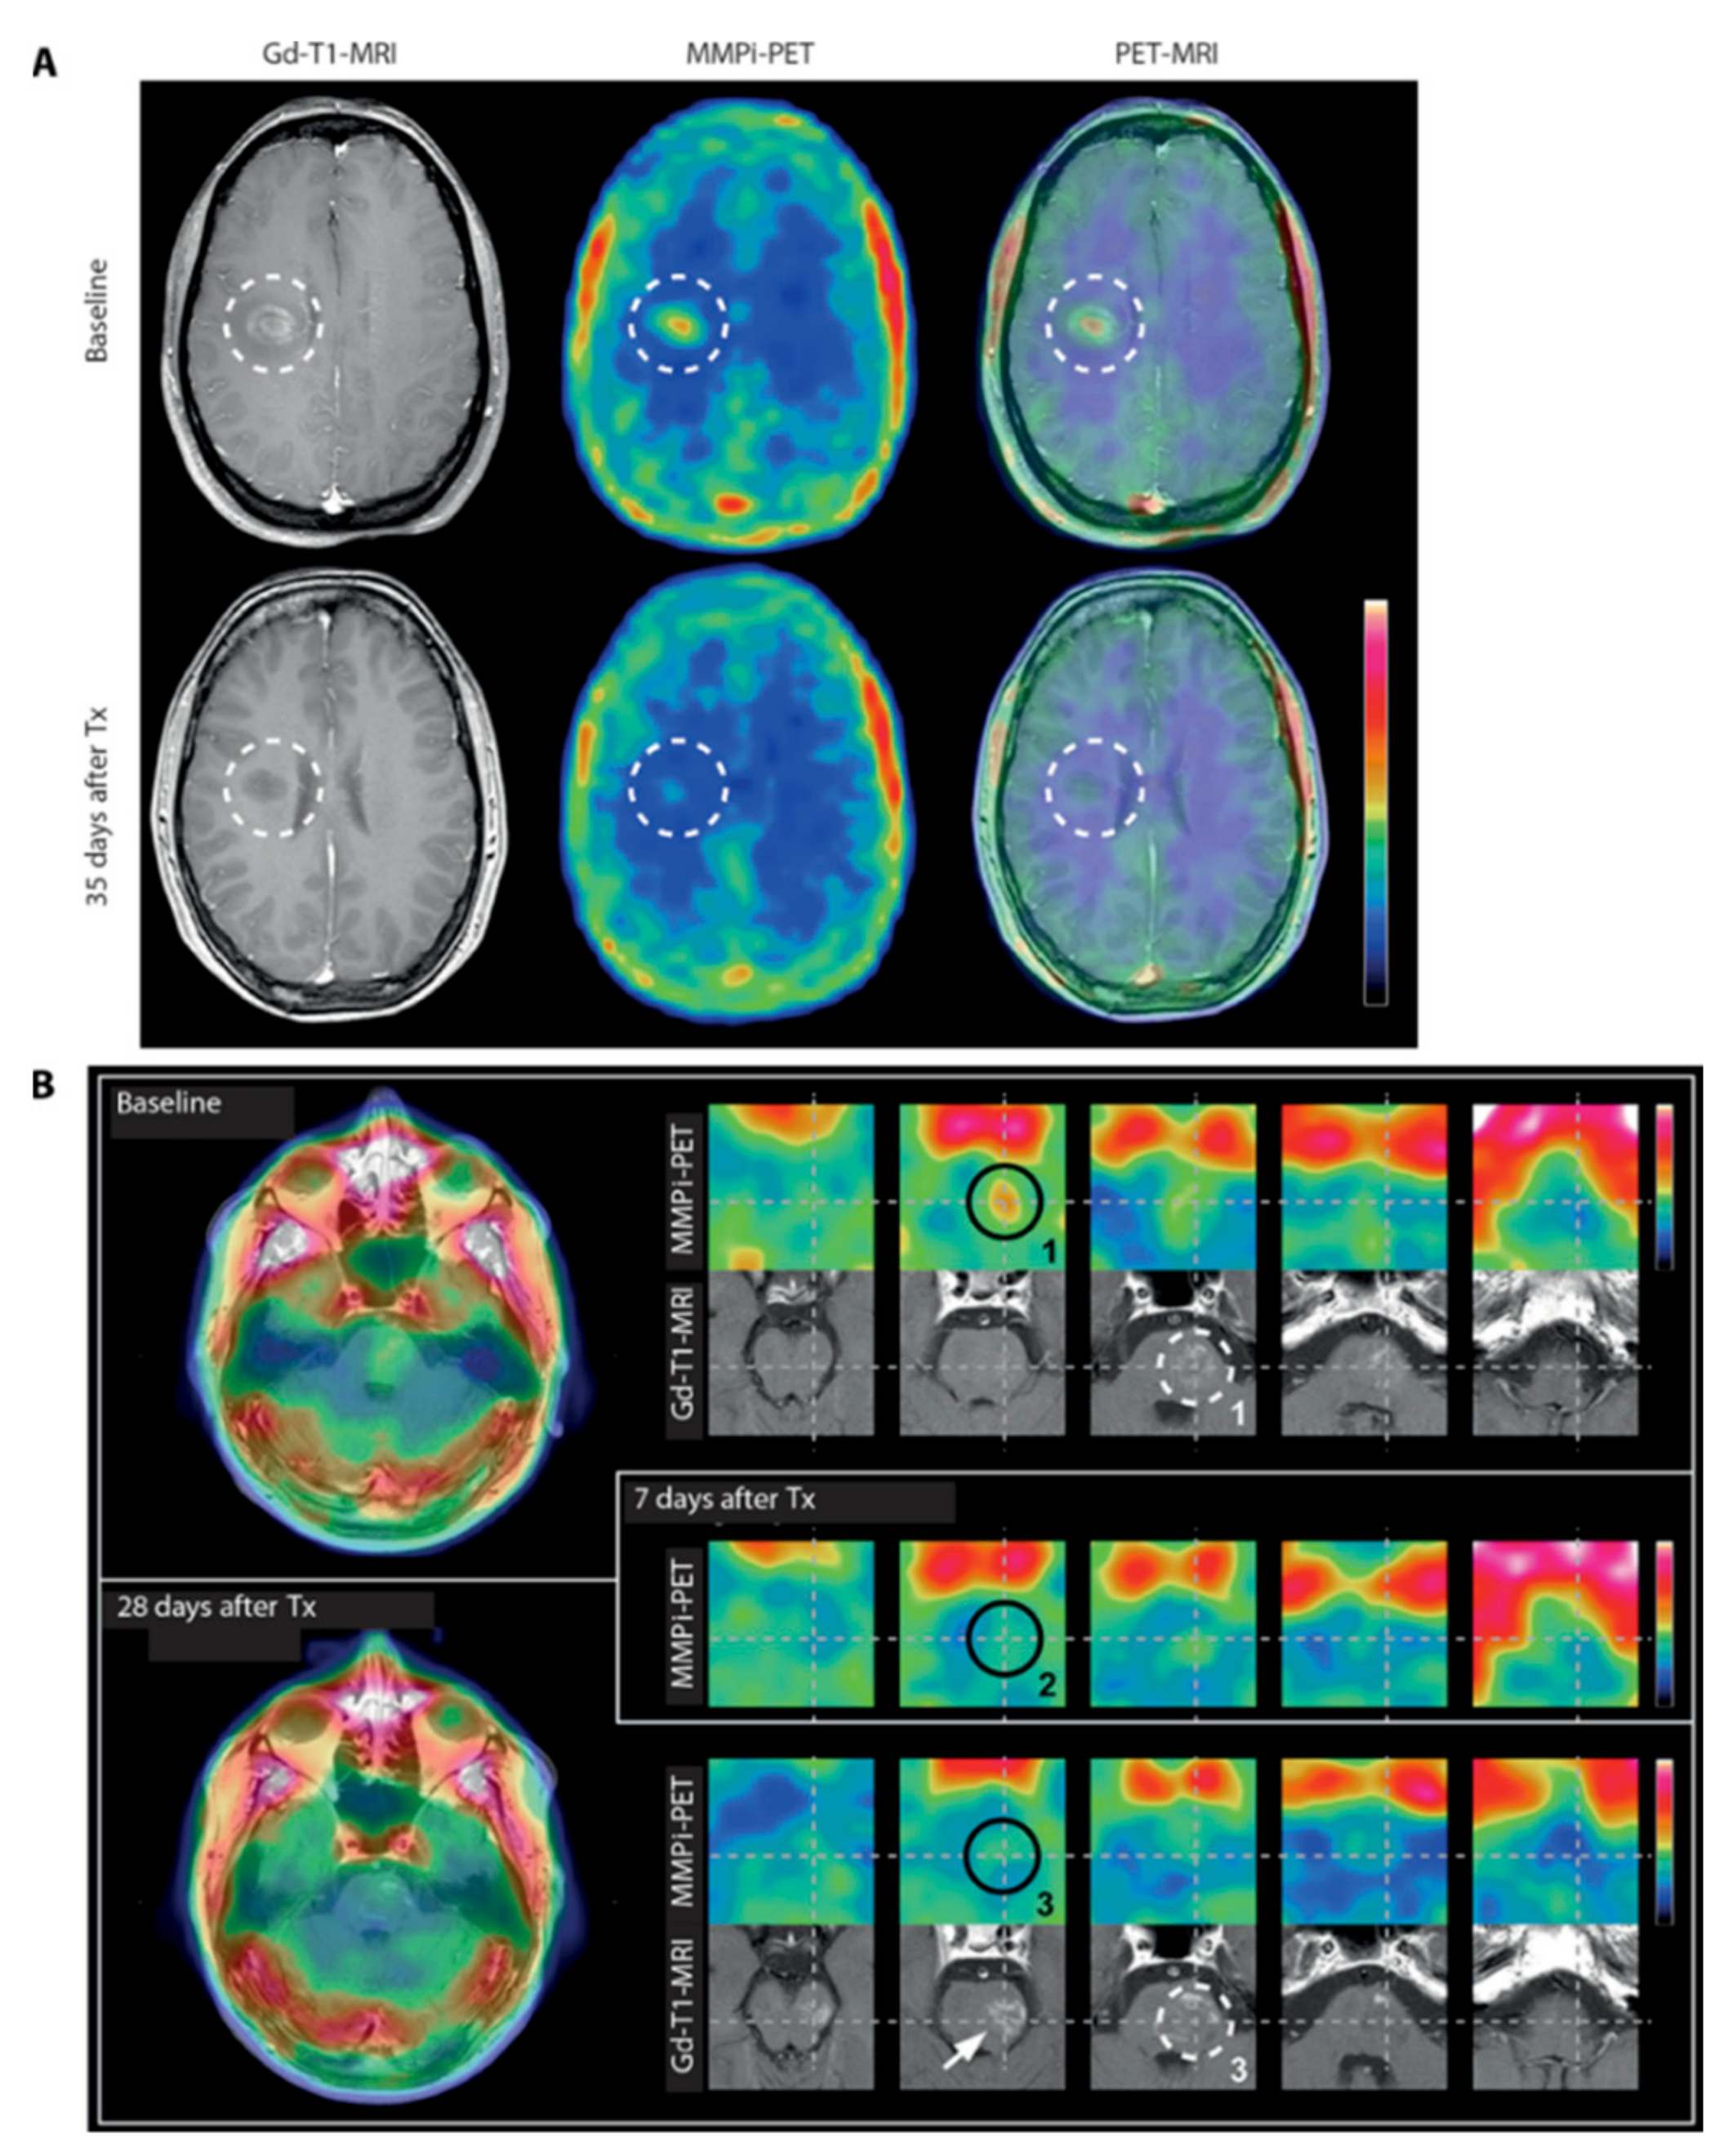

They synthesized [18F]15 using the method previously described by Wagner et al. [104] and used it for translational PET imaging in MS patients. A total of five patients with known or suspected relapsing-remitting MS (RRMS) presenting acute neurological symptoms participated in a [18F]15-PET study (Figure 9). All patients with the up-regulation of activated MMP-9 in cerebrospinal fluid samples exhibited a higher uptake of [18F]15 into the brain (Figure 9).

Figure 9.

MMPI-PET [18F]15 and Gd-T1-MRI in MS patients before and after anti-inflammatory treatment. (A) [18F]15 and Gd-T1-MRI of patient #6 representing an acute attack of RRMS (EDSS 2.0) at baseline (top) and at 35 days after treatment (Tx) (methylprednisolone) (bottom); white dashed circles mark colocalization of the MMPI-PET signal and contrast enhancement in the MRI scan, which resolves by 35 days after treatment, correlating with a residual MMPI-PET signal. Left: Gd-T1-MRI. Middle: [18F]15 scan 30 to 60 min after injection co-registered to the Gd-T1-MRI scan. Right: An overlay of Gd-T1-MRI and (PET-MRI). (B) Patient #2 represents an acute attack of RRMS. Left: Single co-registered [18F]15 (30 to 60 min after injection) and Gd-T1-MRI slice at baseline (top) and 28 days after treatment (1 g of methylprednisolone, three times per day) (bottom). Right: Five consecutive PET (upper row) and corresponding MRI (bottom row) slices at baseline (top panel), 7 days after therapy (middle panel, PET only), and 28 days after therapy (bottom panel). Note the intense contrast enhancement in Gd-T1-MRI (maximum, white dashed circle #1) with spatially adjacent but not identical MP activity (black circle #1) at baseline. Reduced MMPI-PET signal at 7 days after therapy (black circle #2), and by 28 days after therapy, the MMPI-PET signal remains low (black circle #3), but the Gd-T1-MRI signal now colocalizes to the original MMP active area from the baseline scan. Reprinted with permission from [103] Copyright © 2016, American Association for the Advancement of Science.